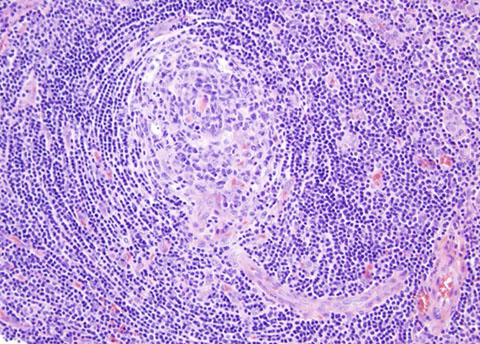

Hyperplastic lymphoid follicle. Germinal center with sharply demarcated mantle zone (solid blue arrow). Dark zone of GC with starry-sky pattern (open blue arrow) and light zone (open black arrow) with small centrocyte predominance [2]

High magnification of GC with centroblasts (solid blue line) mixed with histiocytes with clear cytoplasm with nuclear fragments (open black line) and frequent mitoses (curved black line)

Micro: many large follicles, variety of size / shape

- have central germinal center (GC) and well-demarcated mantle zone

Germinal center (GC): centroblasts and centrocytes, few T-cell, scattered histiocytes

- usually are polarized (have light and dark zones)

-- dark zone: many centroblasts (with high N:C ratio) and mits

-- light zone: predominantly centrocytes and follicular dendritic cells

Centroblasts: 3-4x size of small lymphs; have 1-3 nucleoli

Mantle zone: concentric layers of small naive (non-antigen exposed) B-cells